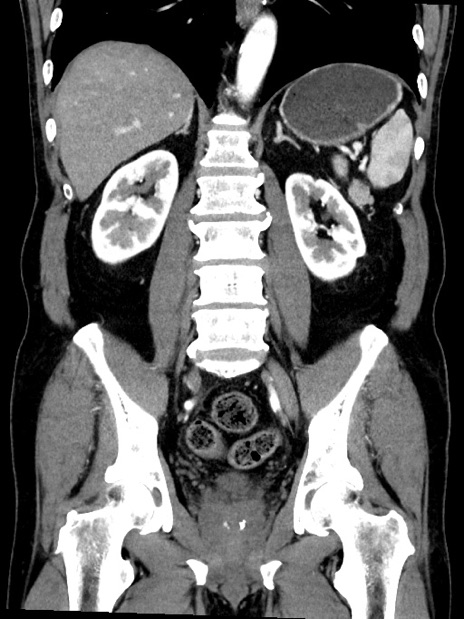

症例35(冠状断像)

【症例】70歳代 男性

【主訴】腹部膨満、嘔吐

【現病歴】昨日より腹部膨満感出現。本日増悪し、仙痛出現。嘔吐あり、受診。

【既往歴】糖尿病、胆摘後

【身体所見】BP 149/80mmHg、HR 74/min、BT 35.9℃、腹部:膨満、軟、圧痛なし。腸雑音減弱あり。上腹部正中切開瘢痕あり。

【データ】WBC 13500、CRP 1.72